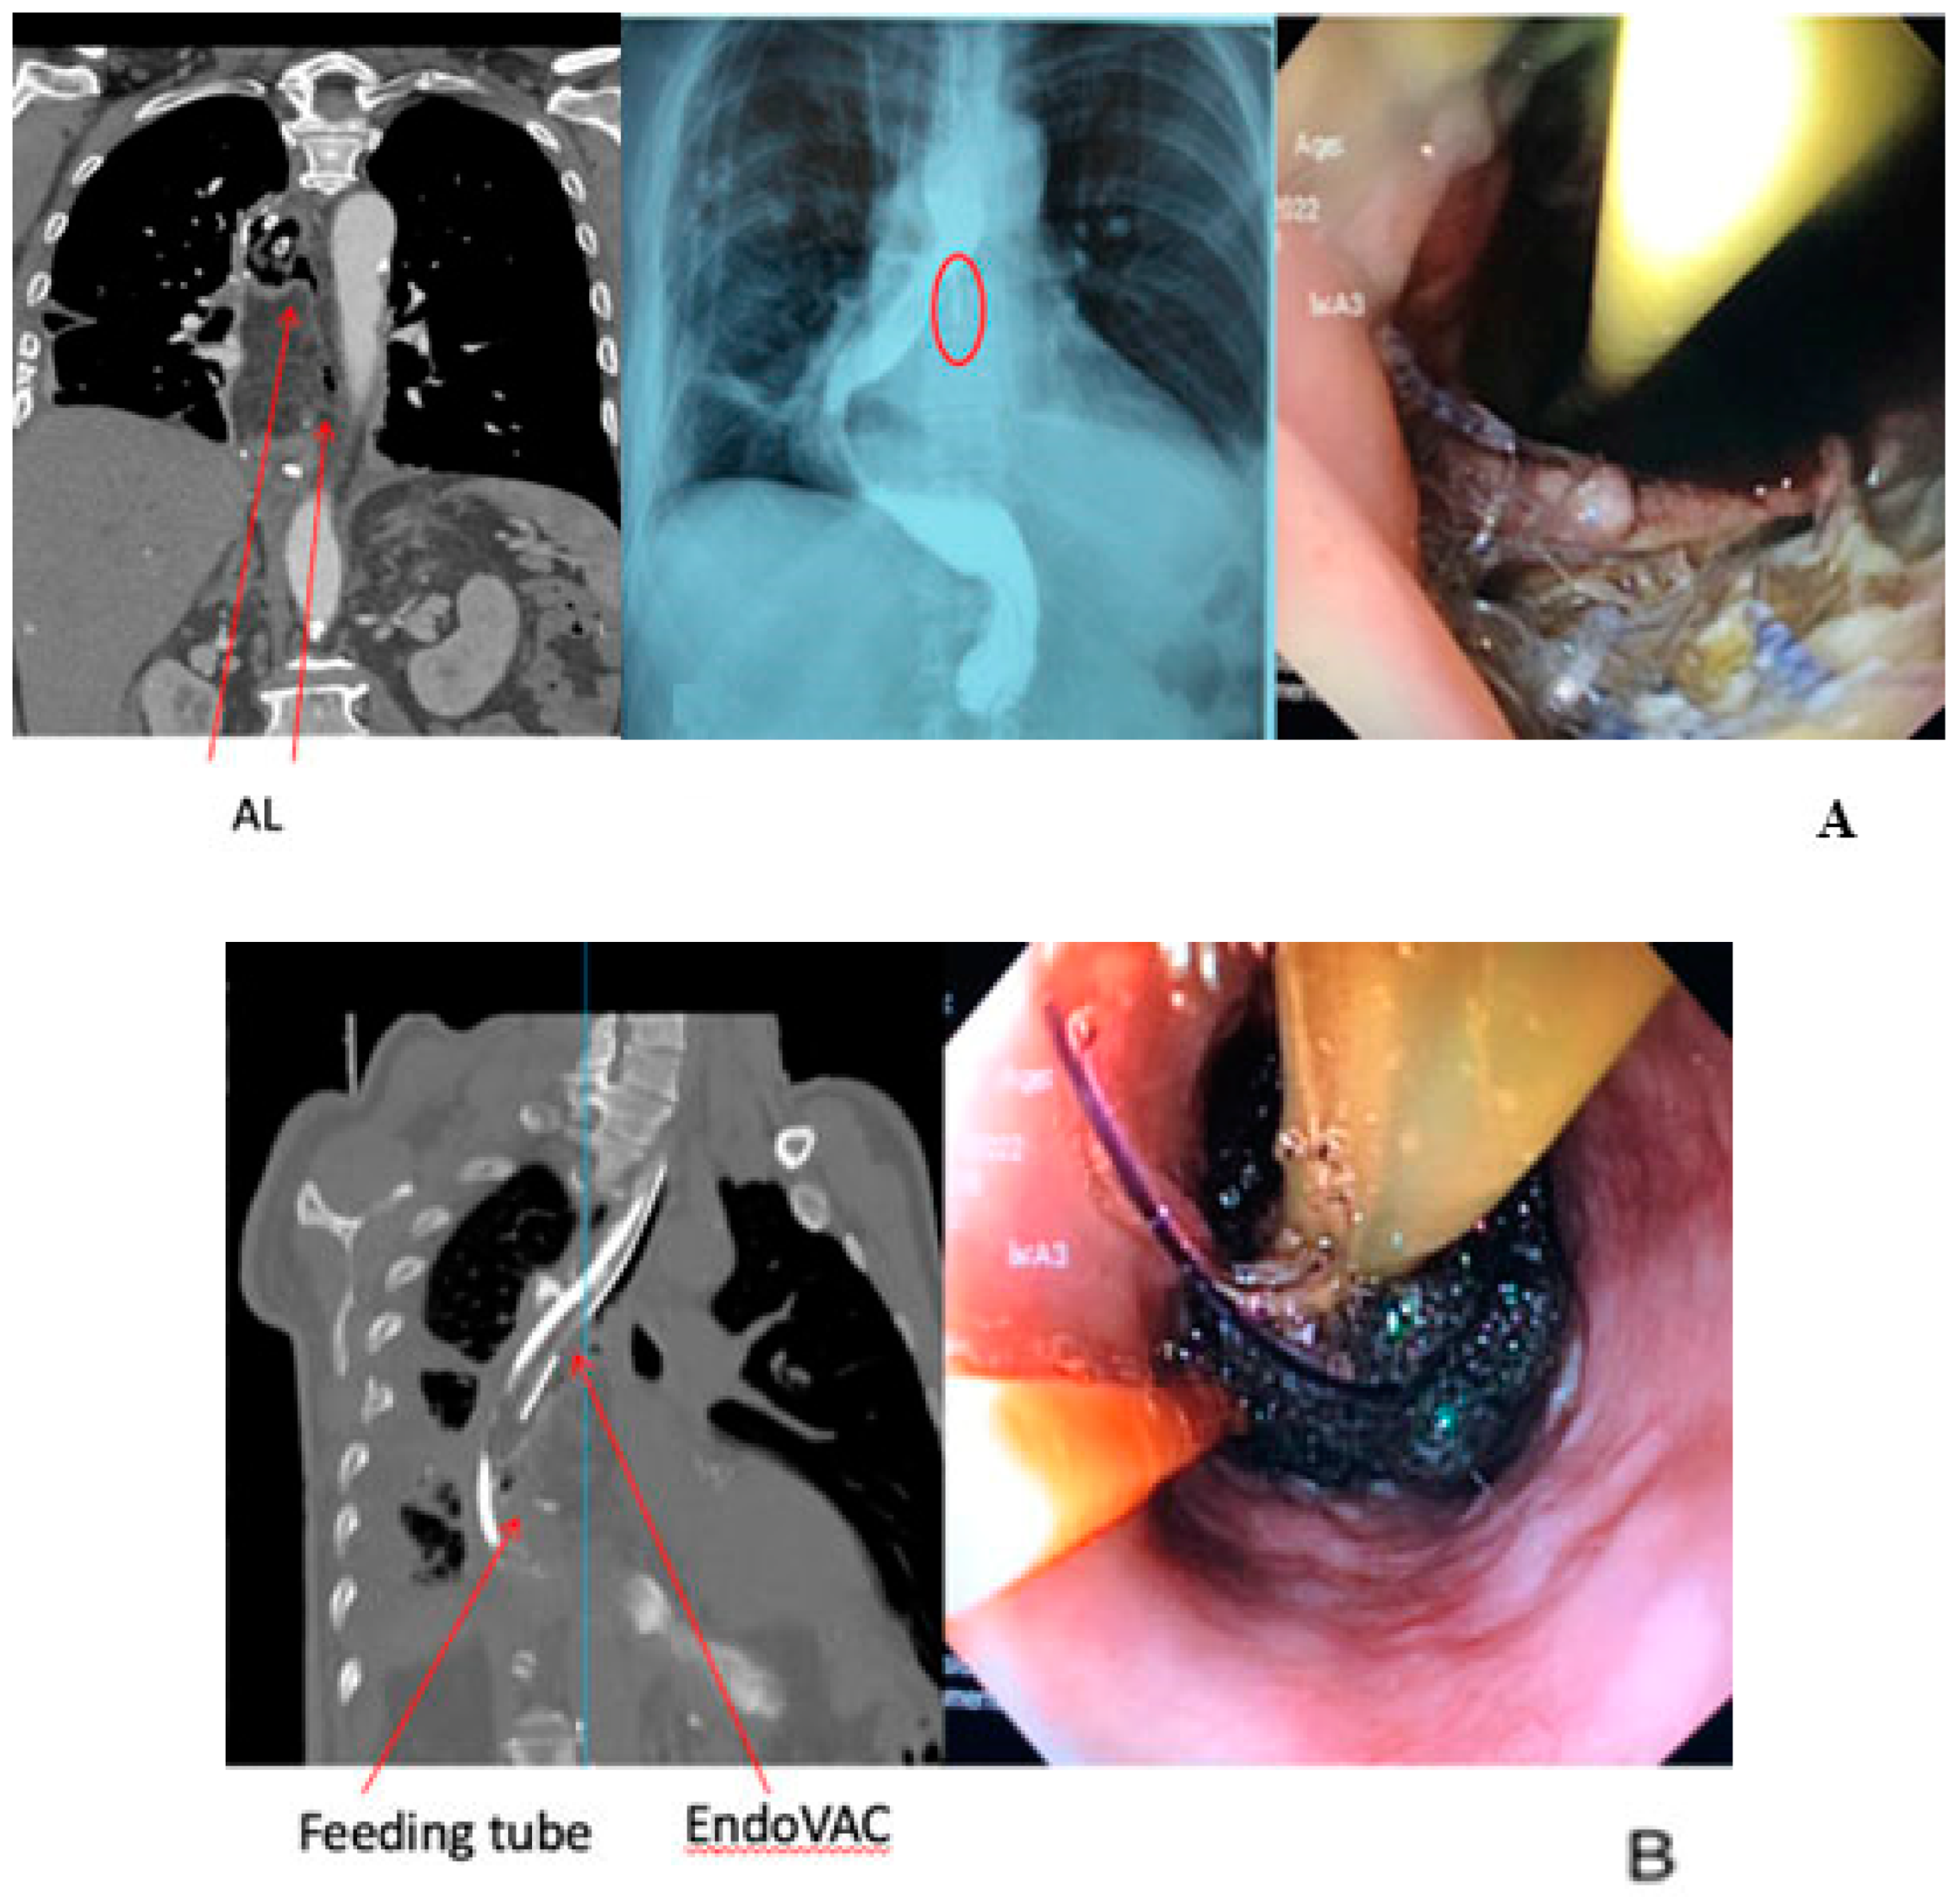

The EndoVAC application protects the cavity from exposure to highly acidic gastric juice which could be erosive, while as mentioned above it removes the microbial burden and the excess of the interstitial fluids. A variation among several authors has been documented with others proposing wider intervals for the changes (Lee et al. conducted changes every 4 to 7 days [64]) and others administering lower levels of intracavitary pressure (Gutschow et al. conducted EndoVAC therapy with 75 mmHg [65]). Loske et al. applying continuous negative pressure of 125 mmHg reported sufficient rates of wound sealing and drainage [66]. A recent investigation utilizing a porcine model for esophagectomy demonstrated that employing EndoVAC therapy at a pressure of −125 mmHg markedly augmented tissue perfusion in ischemic gastric conduits. This finding suggests a potential preemptive application of EndoVAC therapy for gastric conduits exhibiting compromised arterial perfusion or venous congestion [69]. The above are presented in a clinical case illustration in Figure 1.

Figure 1. A 56-year-old male patient underwent an Ivor-Lewis esophagectomy post neo-adjuvant chemoradiotherapy (CRT). The surgical procedure included a hand-sewn esophagogastric anastomosis. (A) An AL was diagnosed on the 7th postoperative day. Arrows and circle show the AL. (B) Successful closure of AL was achieved after 27 days with 8 sessions of endoscopic vacuum therapy.